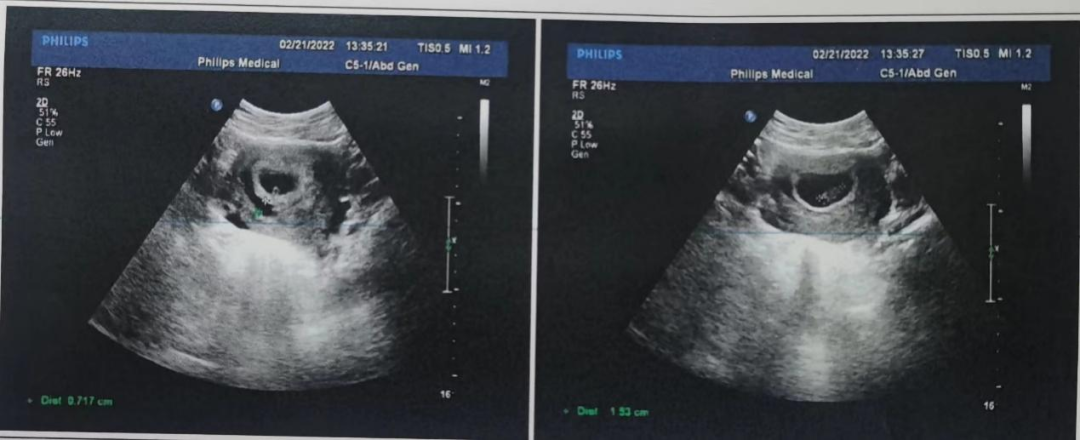

2021-11-29再次复查阴超提示宫腔内见不均回声,大小约3.3cm*1.4cm(图1),查HCG:219.23mIU/mL,建议宫腔镜手术。患者坚决要求药物保守治疗,告知其相关风险后,并充分知情同意,完善相关检查,排除药物禁忌后,开始予雌孕激素序贯方案联合米非司酮、血府逐瘀胶囊行药物保守治疗1疗程。用药期间阴道流血止,无明显腹痛。

图1:不全流产宫腔残余物图像

2021-12-20复查阴超提示宫腔内未见异常(图2),查HCG正常范围。

图2:用药1疗程停药撤退性出血干净后宫腔阴道超声图